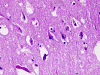

The overall tissue preservation is less than optimal because of postmortem autolysis. Panel A and B are taken from the cerebellum. The molecular layer, Purkinje cell layer, and internal granular layer are included (Panel A). Solitary eosinophilic intracytoplasmic inclusions of variable size are present in the Purkinje cells. No inflammatory cell infiltration is present in the cerebellum. The vacuolar spaces (Panel B) is partly due to autolysis and partly due to hypoxic/ischemic changes. Pyramidal cells in the hippocampus (Panel C), cortical neurons in parietal lobe (Panel D) and other neocortical areas adopted an elongated and contracted contour with loss of nuclear details. These are histologic features consistent with hypoxic/ischemic changes. Similar to the cerebellum, solitary eosinophilic cytoplasmic inclusion bodies are present and there is no inflammatory cell infiltration. Multiple eosinophilic cytoplasmic inclusion bodies within a single neuron are occasionally found. Some of these neurons containing multiple inclusions from the substantia nigra are illustrated in Panel E. Although inflammatory cell infiltration is scant in the cerebrum and cerebellum, perivascular chronic inflammatory cell infiltrations are common in the medulla (Panel F and G), in the paravertebral sympathetic ganglion (Panel H and I) and in the spinal cord (not shown). Intracytoplasmic inclusions, however, are not found in the medulla, spinal cord, and paravertebral sympathetic ganglion. Under the electron microscope, rod-shape or bullet-shaped viral particles are found (Panel J).

The brain and spinal cord may appear swollen but are usually free of focal lesions. Histopathologically, rabies is a widespread polioencephalomyelitis. Leptomeningeal and parenchymal perivascular lymphocytic infiltrations are usually present but often not intense. Neuronophagia can also be seen. The amount of inflammation of the case under discussion is, in fact, on the intense side of the scale. The pathognomonic Negri bodies 10, 11, 12 are sharply delineated, round to oval, eosinophilic, neuronal cytoplasmic inclusions; first described by Negri in 1903 10. These inclusions are often solitary but may also be multiple in a single neuron. Lyssa bodies refer to less well delineated and more pleomorphic neuronal cytoplasmic viral inclusions. Babes’ nodules refer to clusters of microglia that remain after destruction of neurons. When immunohistochemistry is employed, the distributions of viral antigen are far more extensive than that estimated by conventional light microscopy 13. Negri body and rabies viral antigen as demonstrated by immunohistochemistry are most commonly seen in large neurons of the hippocampus (Pyramidal cells), cerebellum (Purkinje cells), thalamus, basal ganglia, cerebral cortex and in the brain stem, especially gray matter of the pons and medulla. They are also found in spinal cord motor neurons and dorsal root ganglion, especially in the paralytic form.  Immunohistochemistry also demonstrated rabies viral antigen in astrocytes and oligodendrocytes 13. Characteristically, a striking discrepancy between the degree of inflammation and amount of inclusion bodies is observed, as in our case, in many cases.